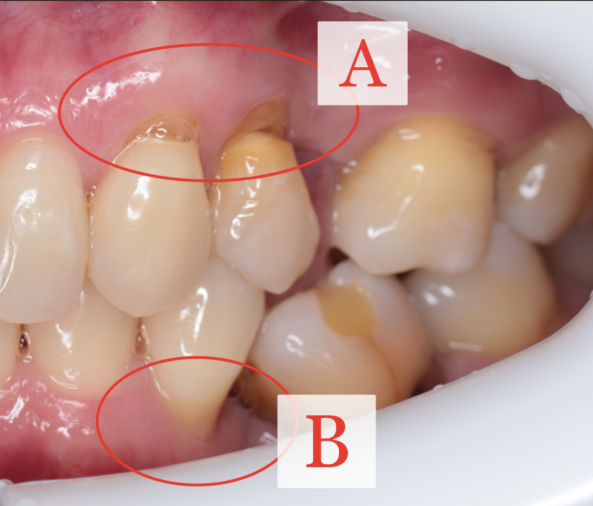

В рассматриваемом случае можно выделить две зоны - A и B, в которых рецессия развивается по разным сценариям.

Зона A. Рецессия на фоне клиновидного дефекта и перегрузки

В зоне A рецессия связана с выраженным клиновидным дефектом.

Край десны располагается прямо по верхней границе клиновидного углубления. Это важная диагностическая деталь: здесь проблема связана не только с мягкими тканями, но и с изменением пришеечной зоны зуба.

Дополнительная особенность - у 23 и 24 зубов практически не стёрт щёчный бугор.

Это может указывать на повышенную нефункциональную нагрузку, которая сформировалась из-за отсутствия второго премоляра.

Зона B. Другой механизм - положение корня и дефицит костной опоры

В зоне B рецессия развивается по другому сценарию.

Здесь ключевую роль играет:

• положение корня в альвеолярном отростке

• дефицит костной пики дистально

Другими словами, проблема также связана с отсутствующим зубом, но не через клиновидный дефект, а через недостаточную костную и мягкотканную поддержку.

Внешне рецессии в зоне A и зоне B могут выглядеть очень похожими.

Но механизм их возникновения разный.

• В зоне A ключевым фактором является клиновидный дефект и перегрузка.

• В зоне B - дефицит костной опоры и положение корня.